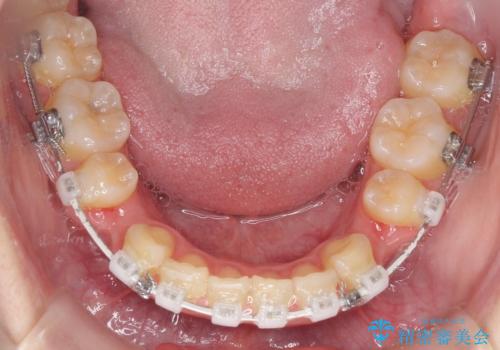

- 審美装置

- 2年3ヶ月

- 10-30回